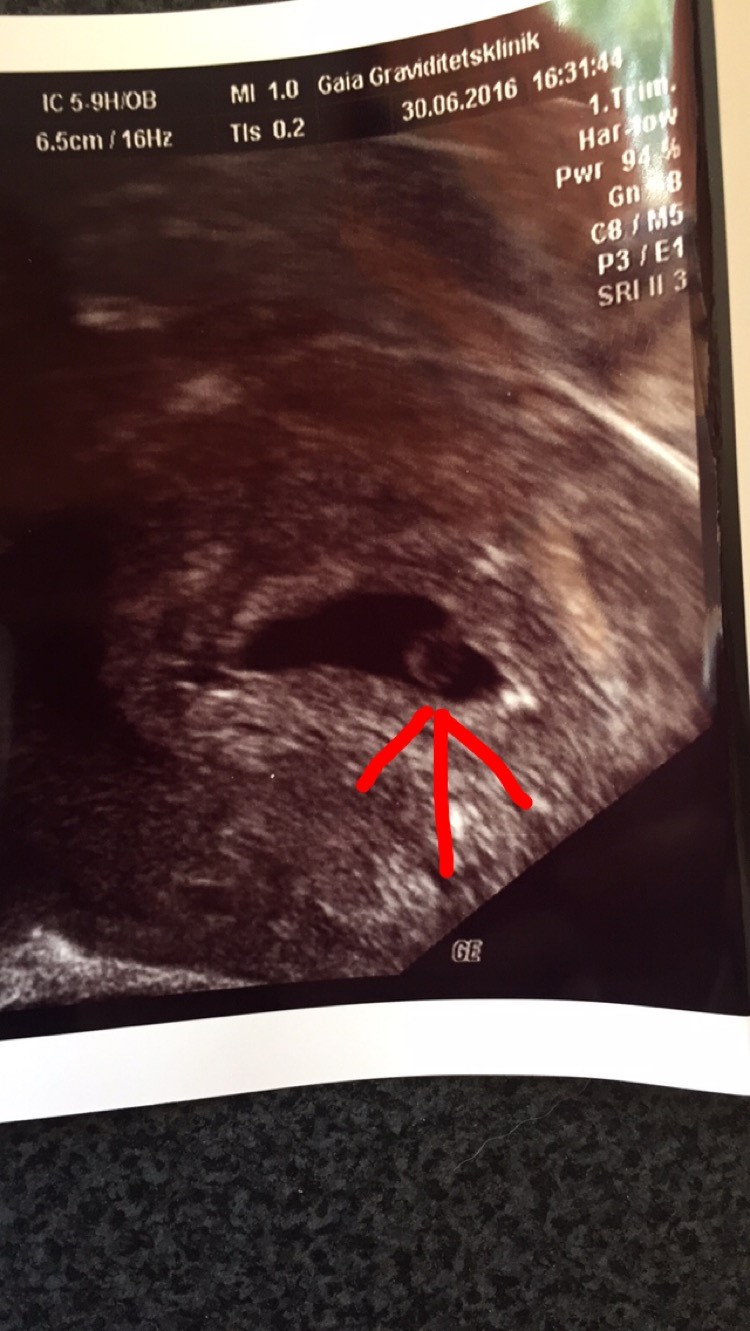

jeg er noget spændt på hvad der gemmer sig der inde. Og om det ligger rigtigt, som det selvfølgelig gør

Bliver så sjovt at se hvor mange der gemmer sig